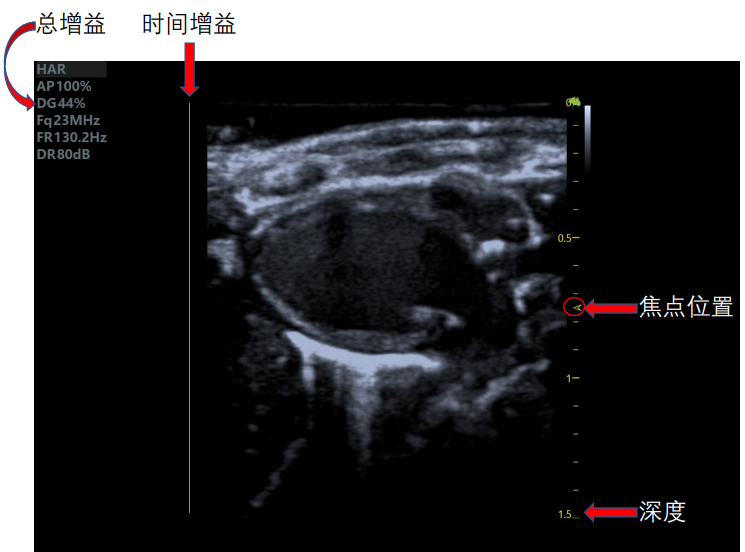

超聲波因其頻率超過(guò)了人耳的聽(tīng)覺(jué)范圍所限,所以稱(chēng)之為超聲波。利用人體超聲產(chǎn)生的波在人體內(nèi)傳播時(shí),通過(guò)示波屏顯示體內(nèi)各種器官和組織對(duì)超聲的反射和減弱規(guī)律來(lái)診斷疾病的一種方法。 超聲波具有良好的方向性,在人體內(nèi)傳播過(guò)程中,遇到密度不同的組織器官,即有反射、折射和吸收等現(xiàn)象產(chǎn)生。 根據(jù)示波屏上顯示的回波距離、弱強(qiáng)和多少,以及衰減是否明顯,可以顯示體內(nèi)某些臟器的活動(dòng)功能,并能確切鑒別出組織器官是否含有液體或氣體,或一些實(shí)質(zhì)性組織。 產(chǎn)生波分為多種波形,小動(dòng)物超聲成像系統(tǒng)主要用于M型法,其主要是根據(jù)體內(nèi)心臟等結(jié)構(gòu)活動(dòng),記錄其與胸壁間的回聲距離變化曲線,從曲線圖上清晰認(rèn)出心臟的相關(guān)特征,可用于診斷多種心臟疾病。 如何得到一個(gè)準(zhǔn)確的數(shù)據(jù)及好看的心臟切面圖?接下來(lái)請(qǐng)看仔細(xì): 一個(gè)好看的心臟切面圖需要注意超聲掃查的切面選取及手法、總時(shí)間及時(shí)間增益、焦點(diǎn)位置、深度。 1.心臟切面手法:

4.增益調(diào)節(jié):增益調(diào)節(jié)至看到組織且不刺眼即可,增大增益會(huì)使圖像更加明亮清晰,降低增益,可減少噪聲,使圖像更清晰。